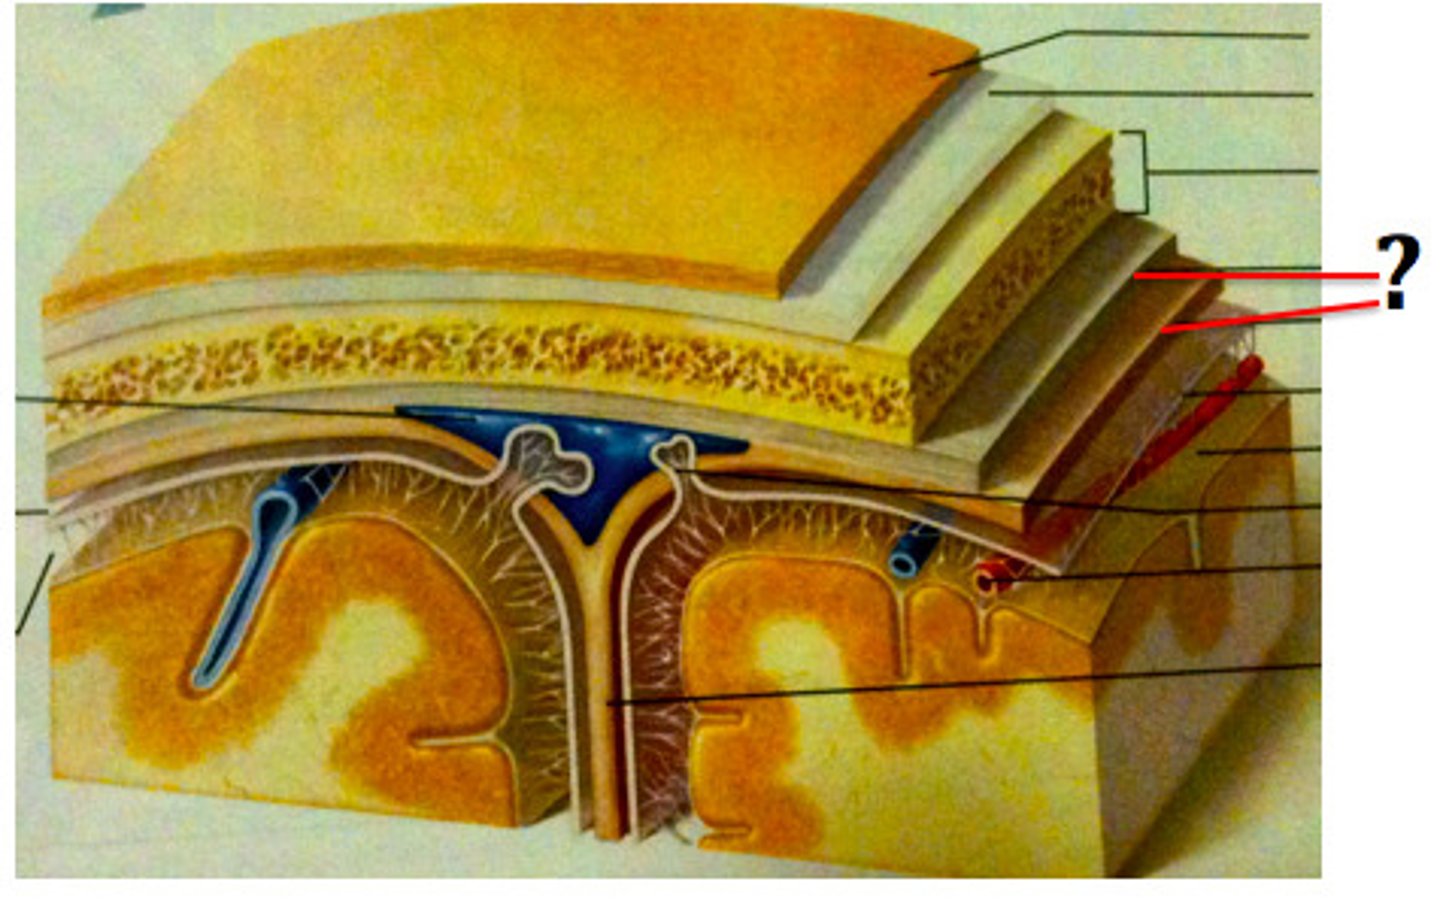

3 layers make up the meninges

dura mater, arachnoid mater, pia mater

dura mater

outer periosteal layer & inner meninges layer

periosteal and meningeal

two layers of dura mater

arachnoid

middle layer of meninges; weblike appearance that attaches it to deepest layer

arachnoid trabeculae

filaments between the arachnoid and pia mater within the subarachnoid space

subdural space

space between dura mater and arachnoid mater

subarachnoid space

skin of scalp

arachnoid mater

pia mater

the delicate innermost membrane enveloping the brain and spinal cord.

leptomeninges

The pia mater and arachnoid together